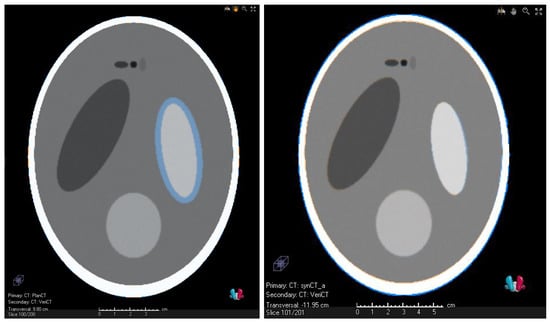

3.1. Validation of the Synthetic CTs—Results

3.2. Preliminary Results of the Clinical Study